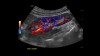

MVI (Micro Vascular Imaging): Kiçik damarların yüksək dəqiqlikli qiymətləndirilməsini təmin edən mikro-damar görüntüləmə rejimi.

Radiantflow™: Kiçik damarların üçölçülü vizuallaşdırılmasını təmin edən texnologiya, MVI ilə birlikdə istifadə edildikdə damar morfologiyasının təhlilini asanlaşdırır.